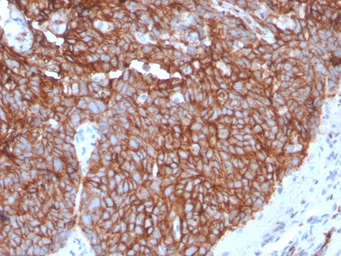

IHC-P analysis of human tongue tissue section using GTX02708 GluT1 antibody [GLUT1/3132R].